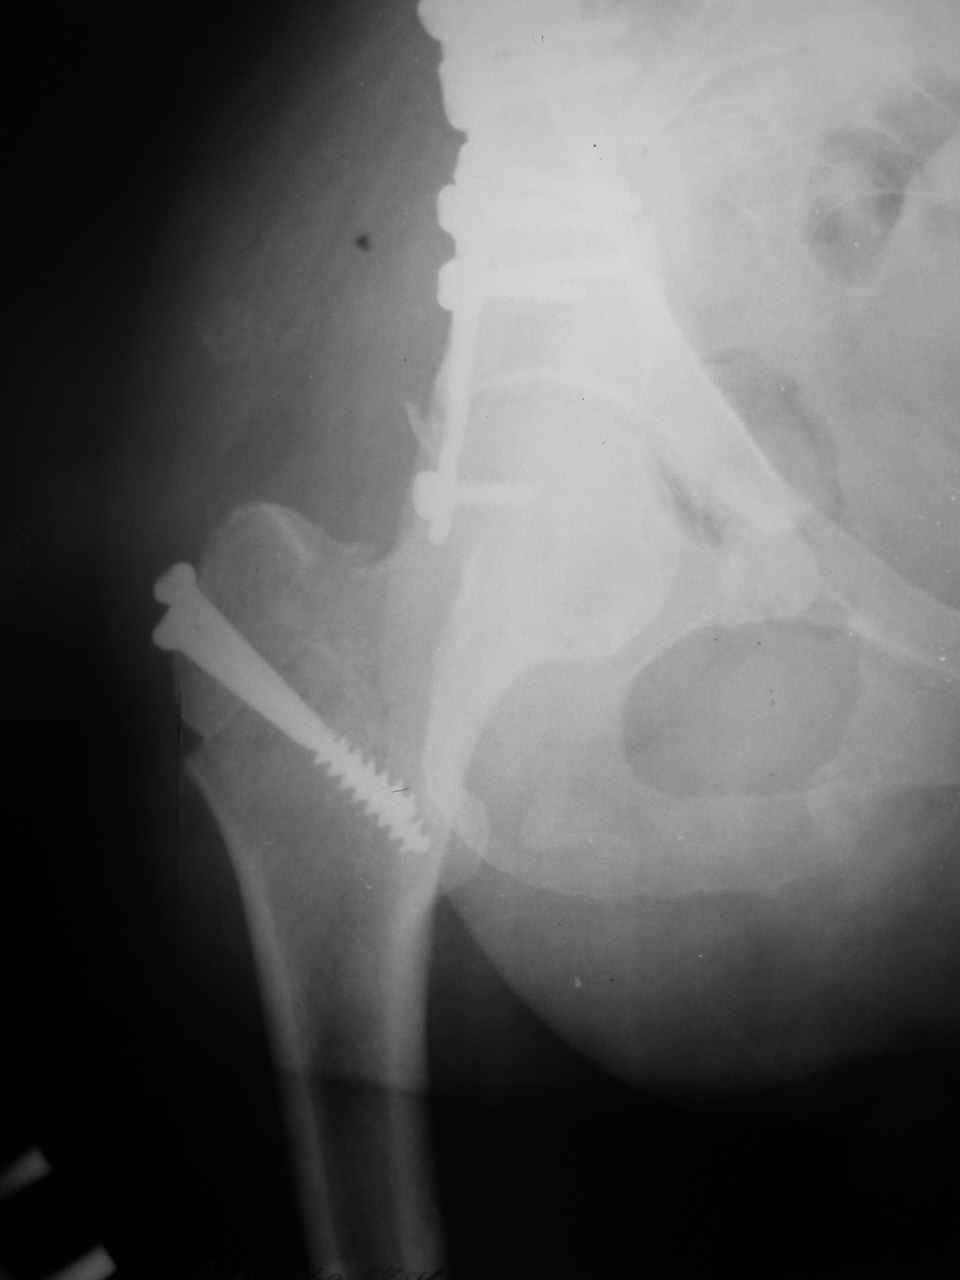

Re: Перелом вертлужной впадины

Смирнов Алексей 09 Ноябрь 2004, 01:17

Снимки и схема